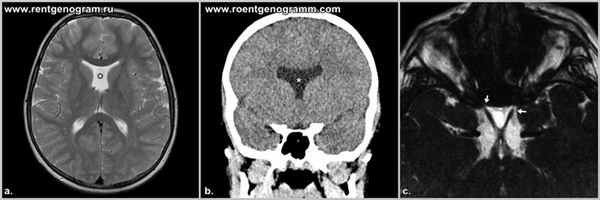

При использовании любой модальности (УЗИ, КТ, МРТ) можно отметить отсутствие прозрачной перегородки, что позволяет заподозрить септооптическую дисплазию. Визуализация остальных характерных признаков зависит от модальности.

В дополнении к расширению боковых желудочков на фоне отсутствующей прозрачной перегородки, компьютерная томография позволяет визуализировать уменьшение размеров зрительного нерва (лучше визуализируется при волюметрическом сканировании и корональных реконструкция) сочетающегося с уменьшением диаметра отверстия канала зрительного нерва.

Магнитно-резонансная томография

МРТ является модальностью выбора для диагностики септооптической дисплазии и позволяет визуализировать:

- уплощение крыши передних рогов боковых желудочков в корональной плоскости

- отсутствие прозрачной перегородки

- гипоплазия воронки гипофиза

- гипоплазия хиазмы и глазных яблок

Септооптическая дисплазия (синдром de Morsier) является одной из форм лобарной голопрозэнцефалий. Характеризуется отсутствием прозрачной перегородки, гипоплазией зрительных нервов, хиазмы и воронки.

Сочетанная гипоплазия зрительных нервов и отсутствие или гипогенезия прозрачной перегородки, в 2/3 случаев сопровождающаяся гипоталамо-гипофизарной дисфункцией.

Прозрачная перегородка не формируется, таким образом отсутствует разделение боковых желудочков, так же отсутствуют межжелудочковые отверстия, связывающие боковые и третий желудочек и в результате образуется единая вентрикулярная полость. Кроме того имеется двустороннее недоразвитие зрительных нервов, диаметр их уже.

По данным МРТ головного мозга прозрачная перегородка не дифференцируется, аденогипофиз и ножки гипофиза не определяются.